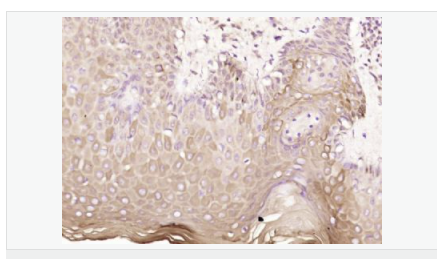

| 产品应用 | WB=1:500-2000 ELISA=1:5000-10000 IHC-P=1:100-500 IHC-F=1:100-500 ICC=1:100-500 IF=1:100-500 (石蜡切片需做抗原修复) not yet tested in other applications. optimal dilutions/concentrations should be determined by the end user. |

| 产品介绍 | Machado-Joseph disease, also known as spinocerebellar ataxia-3, is an autosomal dominant neurologic disorder. The protein encoded by this gene contains (CAG)n repeats in the coding region, and the expansion of these repeats from the normal 13-36 to 68-79 is one cause of Machado-Joseph disease. There is a negative correlation between the age of onset and CAG repeat numbers. Alternatively spliced transcript variants encoding different isoforms have been described for this gene. [provided by RefSeq, Sep 2009] Function: Interacts with key regulators (CBP, p300 and PCAF) of transcription and represses transcription. Acts as a histone-binding protein that regulates transcription. Acts as a deubiquitinating enzyme. Subcellular Location: Nucleus matrix. Predominantly nuclear, but not exclusively, inner nuclear matrix. Tissue Specificity: Ubiquitous. DISEASE: Defects in ATXN3 are the cause of spinocerebellar ataxia type 3 (SCA3) [MIM:109150]; also known as Machado-Joseph disease (MJD). Spinocerebellar ataxia is a clinically and genetically heterogeneous group of cerebellar disorders. Patients show progressive incoordination of gait and often poor coordination of hands, speech and eye movements, due to degeneration of the cerebellum with variable involvement of the brainstem and spinal cord. SCA3 belongs to the autosomal dominant cerebellar ataxias type I (ADCA I) which are characterized by cerebellar ataxia in combination with additional clinical features like optic atrophy, ophthalmoplegia, bulbar and extrapyramidal signs, peripheral neuropathy and dementia. The molecular defect in SCA3 is the a CAG repeat expansion in ATXN3 coding region. Longer expansions result in earlier onset and more severe clinical manifestations of the disease. Similarity: Contains 1 Josephin domain. Contains 3 UIM (ubiquitin-interacting motif) repeats. SWISS: P54252 Gene ID: 4287 Database links: Entrez Gene: 4287 Human Entrez Gene: 110616 Mouse Omim: 607047 Human SwissProt: P54252 Human SwissProt: Q9CVD2 Mouse Unigene: 532632 Human Unigene: 271914 Mouse Unigene: 42932 Rat Important Note: This product as supplied is intended for research use only, not for use in human, therapeutic or diagnostic applications. |